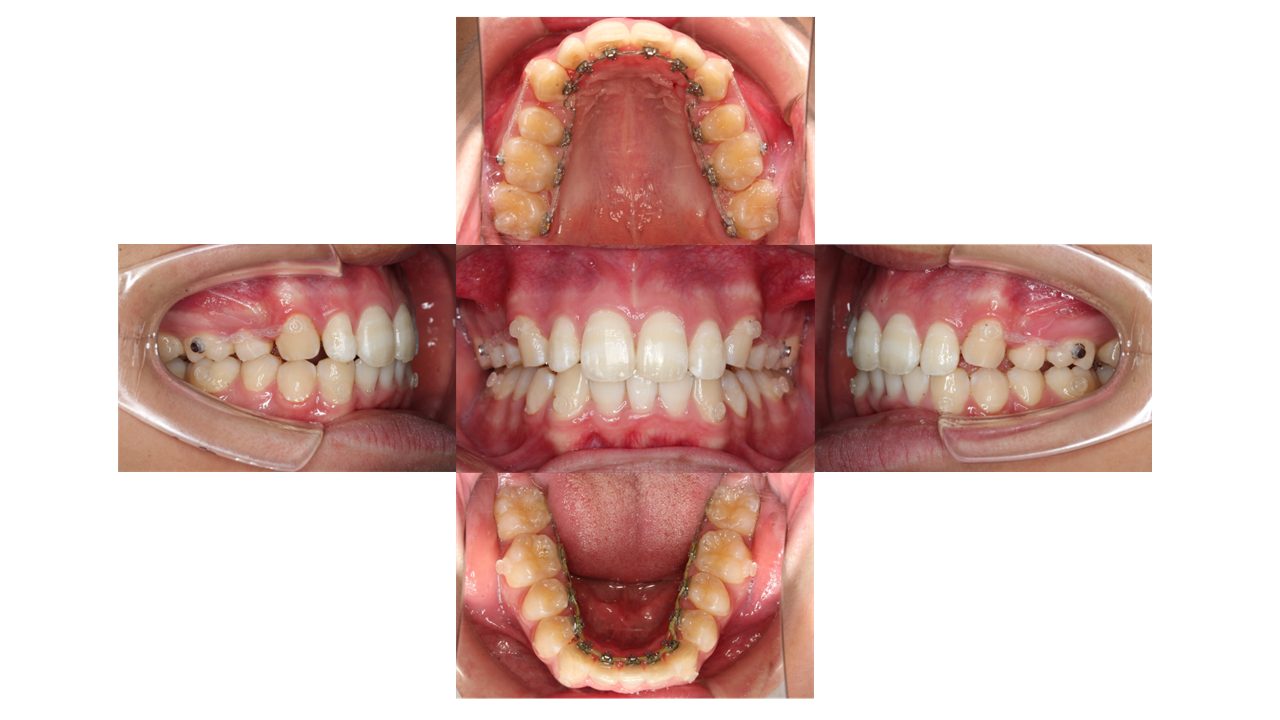

装置装着時の口腔内の状態です。

上顎左右4番目の箇所を抜歯し、裏側矯正(リンガル矯正)で歯を動かしていきます。

現在の歯並びだと、下の歯が上の歯の装置にぶつかってしまう状態のため、上の奥歯にバイトアップという青い材料をつけています。